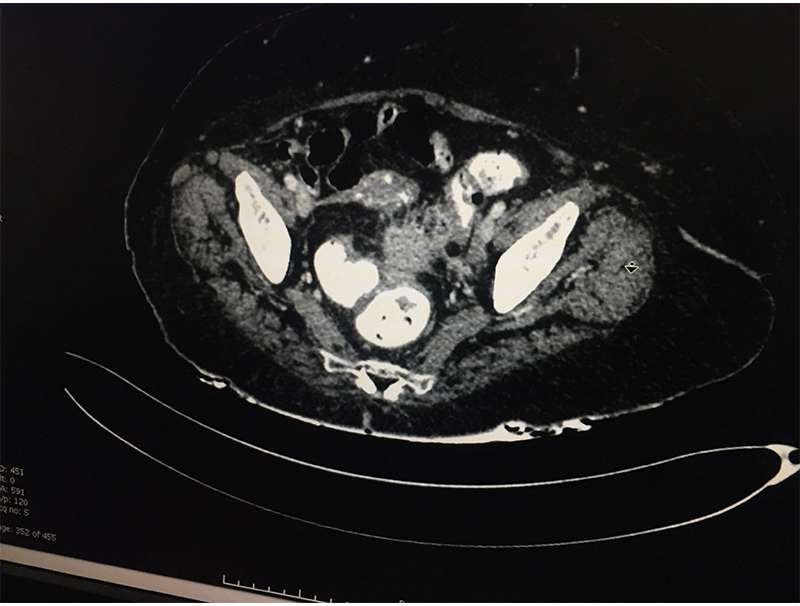

When a patient with acute abdominal pain is diagnosed (clinical suspicion) with a possible diverticulitis, he/she needs further investigations; blood & imaging study (CT scan of abdomen & pelvis) to confirm the diagnosis, rule out complications and plan the treatment based on the laid out guidelines. Most patients without complications & few with complications like contained perforation abscess are managed with antibiotics and occasionally with percutaneous drainage. Few patient require a laparoscopic lavage and drainage. Those with major perforation and fecal contamination require emergency surgery. It is done as an open procedure or by laparoscopic route depending on available expertise & patient condition. The involved sigmoid colon is resected and an end colostomy (bringing out the proximal end) is performed. The colon is reconstructed at a later date once patient has fully settled. If patient is too sick to tolerate a major surgery only a diverting colostomy (to bring the intestine lumen out on surface) is performed.

60 year old lady with an episode of sigmoid diverticular perforation with was managed with antibiotics and other supportive measures. A surgery was avoided at this time. She settled well, however started experiencing recurrent incapacitating abdominal pain due to sigmoid diverticular disease. A laparoscopic sigmoid colectomy and colorectal anastomosis was electively performed. She was discharged on postoperative day 5. She is now completely pain and symptom free.